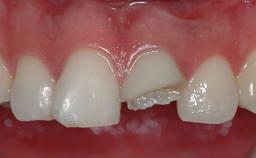

Management of a Fractured Implant Supporting a Screw-retained Metal-ceramic Restoration

The fracture of an implant after it has been restored is one of the most severe complications. It most frequently occurs in partially edentulous jaws (1.5%). Most implant fractures involve implants with a diameter of 3.75 mm made of commercially pure titanium (Eckert 2010). Unfortunately, many cases are not reported or documented by the clinicians involved in resolving the problems created by the fracture. This case report describes the management of an implant fracture at site 36 in a middle-aged male patient. The implant had been restored with a screw-retained metal-ceramic crown.